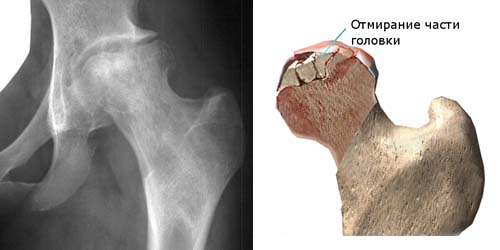

Костные структуры образованы из живых клеток, таким образом, для нормальной жизнедеятельности они нуждаются в постоянном кровообеспечении. Если по какой-то причине снабжение кровью снижается, это приводит к гибели остеоцитов, способствуя деструкции кости. Весь описанный процесс имеет название «остеонекроз», аваскулярным некрозом либо асептическим некрозом кости.

- Патология зачастую поражает область тазобедренного, коленного и плечевого сочленений. Развивается дегенеративный артрит (остеоартрит).

Следующий этап диагностирования — рентгенисследование поврежденной области. На начальных этапах, когда рентген не позволяет выявить некротические явления в кости, поэтому прибегают к сцинтиграфии костных структур либо магнитно-резонансной томографии. Последняя достаточно результативна при диагностировании на начальных этапах.

Хирургическая терапия показана для снижения болевого ощущения и предотвращения сплющивания головки тазобедренного сочленения в результате нагрузки.

При ухудшении состояния больного необходима декомпрессивная оперативная процедура. Она предусматривает просверливание в головке поврежденной кости миниатюрных отверстий, приводящих к уменьшению внутрикостного давления и предотвращению сплющивания.

Асептический некроз тазобедренного и коленного сустава При прогрессирующем некрозе возможно укорочение конечности с развитием хромоты. В запущенных случаях сочленение становится неподвижным и единственным способом лечения является эндопротезирование (замена сустава).